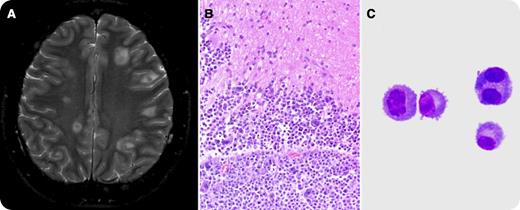

He presented in December 2011 with a severe headache requiring hospitalization. The patient had mild anemia (hemoglobin, 10.6 g/dL) but normal white blood cell and platelet counts. His calcium and creatinine levels were in the normal range. Bone marrow biopsy and serum protein electrophoresis/immunofixation were unremarkable. Computed tomography/magnetic resonance imaging scans of the brain showed multiple foci of hemorrhage with surrounding edema (panel A). A possible infectious etiology or embolic event was suspected clinically. An open excisional biopsy of the right frontal lesion of the brain was performed. The hematoxylin and eosin histologic sections showed brain parenchyma infiltrated by sheets of neoplastic cells with a plasmacytoid cellular morphology with round nuclei, prominent nucleoli, and abundant eosinophilic cytoplasm (panel B). Bi- or multinucleated tumor cells were frequent. The tumor cells were positive for CD138 and CD56 with λ light chain restriction, consistent with plasmacytoma. The cerebrospinal fluid (CSF) contained numerous neoplastic plasma cells (panel C). Isolated plasmacytoma of the brain with CSF involvement after a complete response from an autologous stem cell transplant is a rare event.